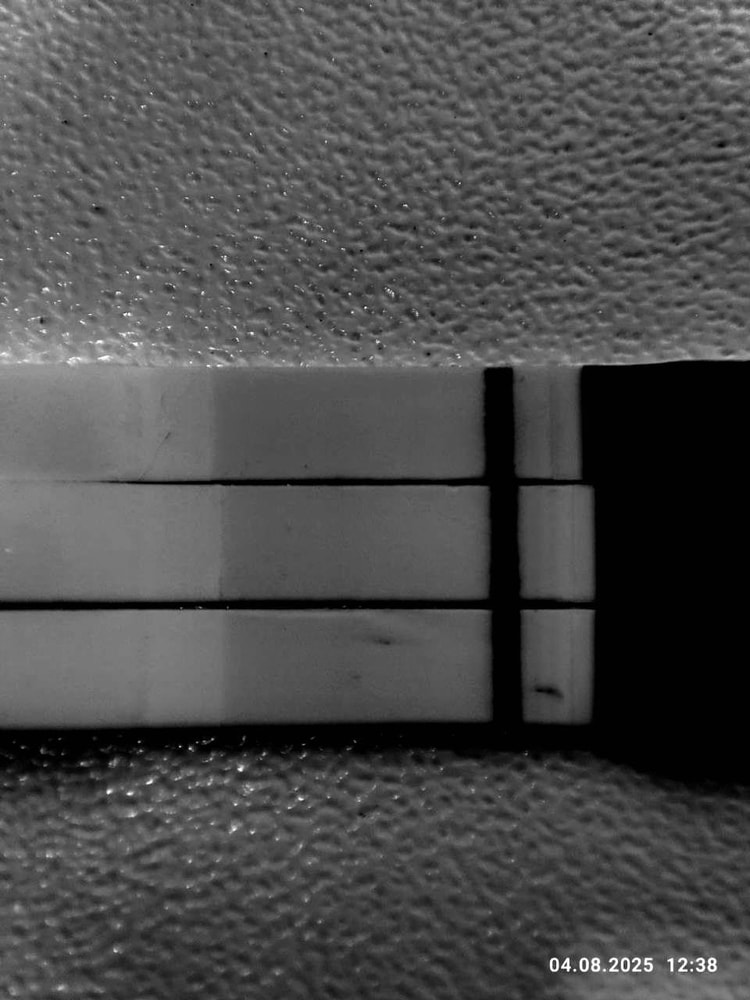

Третий эвик

Мне кажется у эвика что-то есть, но надо повторить однозначтно

Мария Кот, я тоже на эвике вижу, но надо смотреть дальше

Я никогда ничего не вижу на затемненных тестах. Тенюхи видно и так, если они есть.